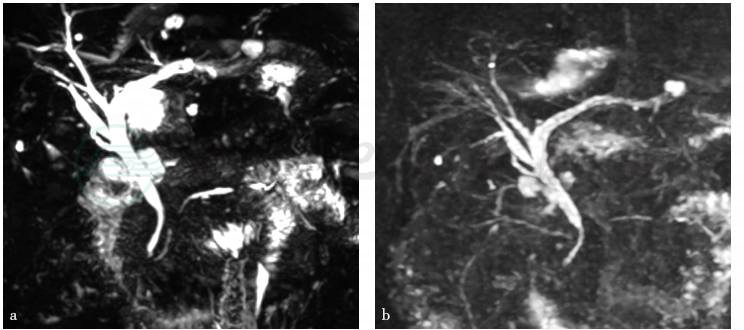

患者于2017年7月12日开始服用泼尼松龙40mg qd,当时IgG4水平为12g/L(正常参考值:0~2g/L)。2017年9月13日复查IgG4为1.35g/L。2018年9月的IgG4水平为0.54g/L。患者服用激素后一般情况好,未再有腹痛发作,定期复查血常规、生化全套、CA199均正常。复查影像学提示胆管狭窄情况明显好转(图6)。

图6 MRCP检查

a. 2017年10月17日;b. 2018年1月19日